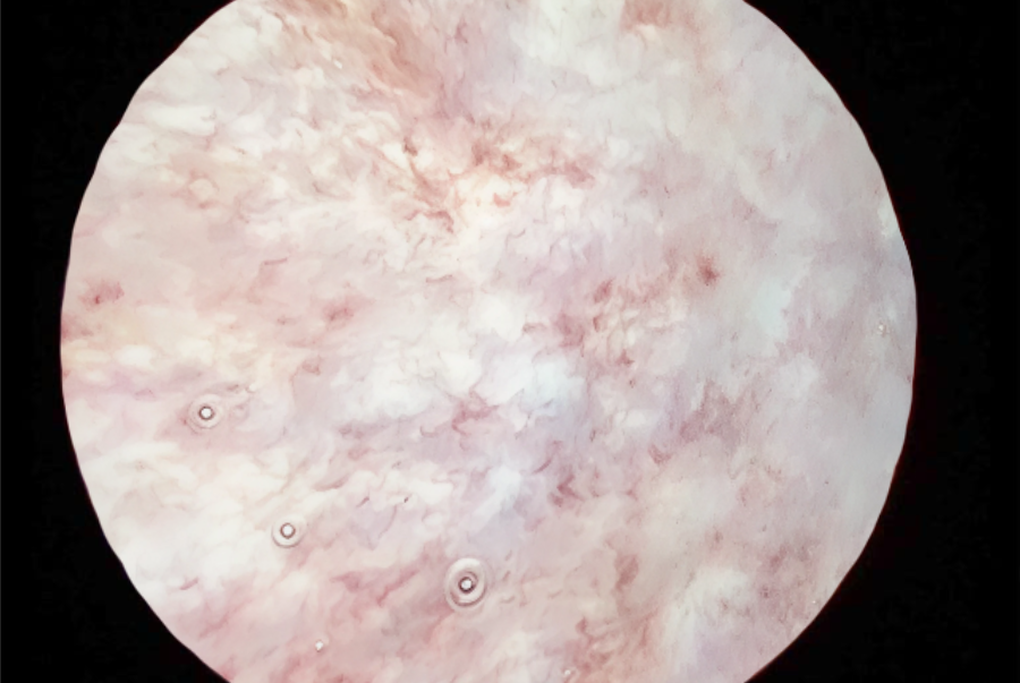

Tại Bệnh viện Đa khoa Hồng Ngọc Yên Ninh, qua thăm khám lâm sàng và nội soi bàng quang, ThS.BS Đặng Văn Duy cho biết niêm mạc bàng quang của bệnh nhân xuất hiện nhiều đốm đỏ, viêm hạt lan tỏa toàn bộ bề mặt.

Bề mặt niêm mạc bàng quang trước bơm xung huyết, nhiều đốm viên (Ảnh: BVCC).